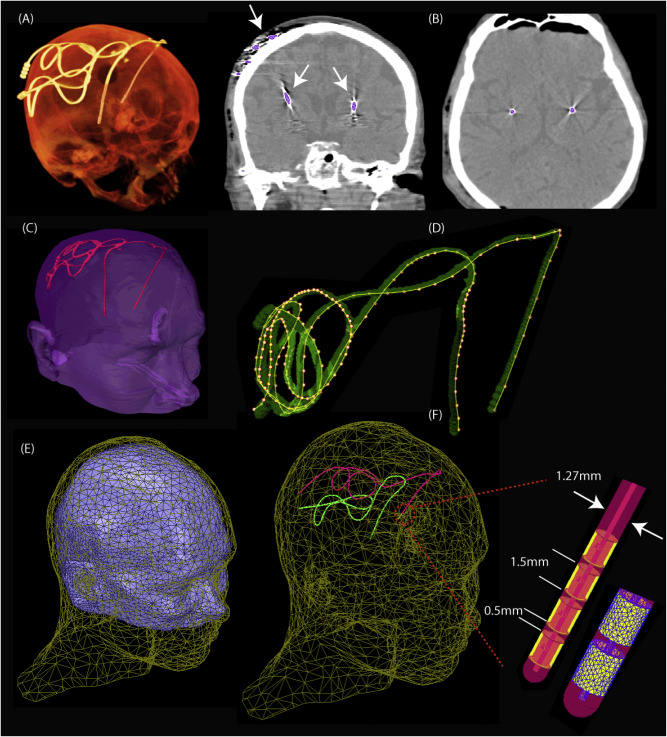

Access to MRI is limited for patients with DBS implants due to safety hazards, including radiofrequency heating of tissue surrounding the leads. Computational models provide an exquisite tool to explore the multi-variate problem of RF implant heating. We used a computational approach to assess RF heating around tips of bilateral DBS leads during MRI at 1.5T and 3T using realistic DBS lead models. A substantial difference was found between the SAR and temperature rise at the tip of right and left DBS leads. Modification of DBS lead trajectory reduced heating in phantom experiments using both conductive wires and commercially available DBS leads.